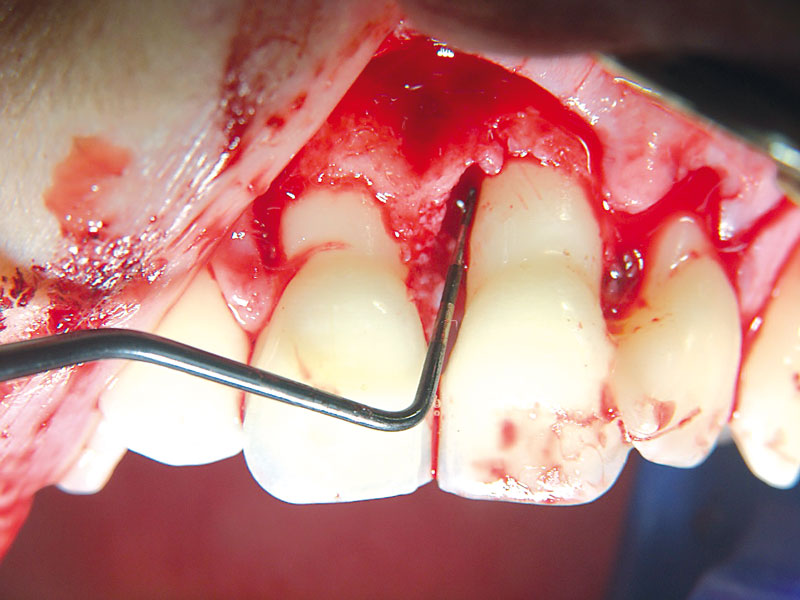

04/11 - Deep intrabony defect on the mesial aspect of tooth 21.Non-contained intrabony defect treated using cerabone®, collprotect® membrane and Straumann® Emdogain® - Dr. T. Schwaar (2)